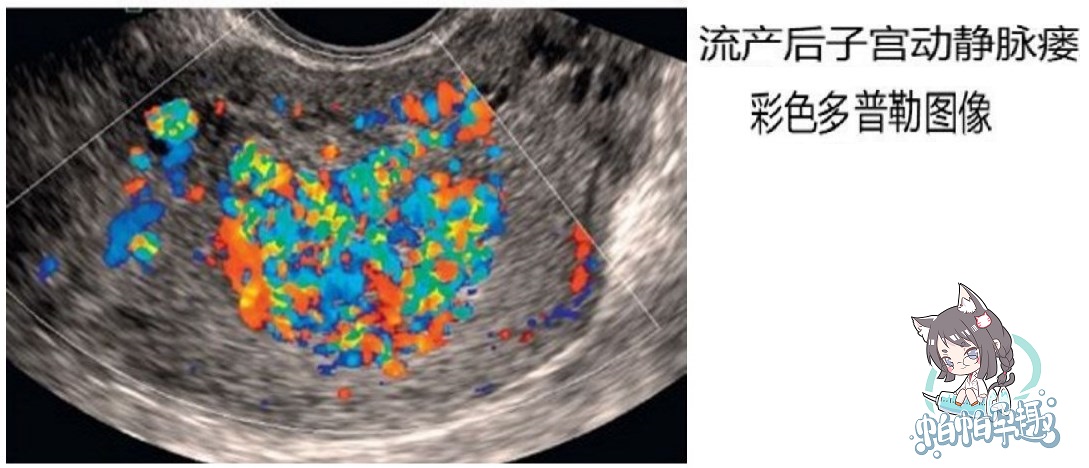

动静脉瘘是动静脉畸形的一种类型,是指动脉和静脉之间不经过毛细血管网,而是动静脉之间吻合,动脉血通过一条异常短路通道直接到达静脉。

子宫动静脉瘘发病率很低,但危害严重,临床症状通常表现为刮宫术后持续性阴道流血,可以不伴有下腹痛,很容易误认为是流产不干净。临床上曾碰到一例早孕流产后阴道流血断续3周不止,误诊为不全流产,反复宫腔镜检查,每次检查一接触病灶就大量出血。后来彩超诊断子宫动静脉瘘,在宫腔镜下局部切除病灶后止血。

引起子宫动静脉瘘的原因有两种:一种是血管在胚胎期发育障碍;另外一种则与流产、刮宫、分娩、剖腹产等创伤因素,以及感染、肿瘤等病理因素有关。创伤后动脉与静脉直接吻合形成交通。彩色多普勒超声检查可以明确诊断,血管造影可以精确定位。 诊断之前需要排除妊娠和滋养细胞疾病。